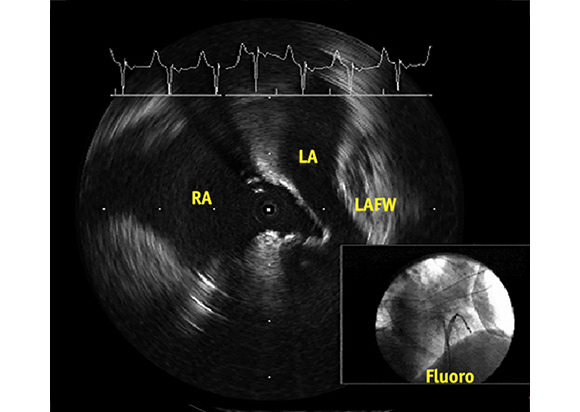

Unique Vision: 360° Views and Detailed Near-Field Resolution

The ULTRA ICE PLUS Catheter generates a cross-sectional and panoramic 360° image perpendicular to the catheter, with the tip as a central reference point. This allows the user to visualize structures (such as the fossa) directly adjacent to the catheter tip and still see a detailed cross-section of the entire septum.

Crossing to the Septum to Help Guiding Left Sided Procedures

A key application for the ULTRA ICE PLUS catheter involves crossing the septum and then monitoring and helping to guide left-sided procedures. In this setting, ULTRA ICE PLUS catheter is designed to allow the user to:

• Visualize left atrial anatomy

• Confirm catheter location relative to the anatomy